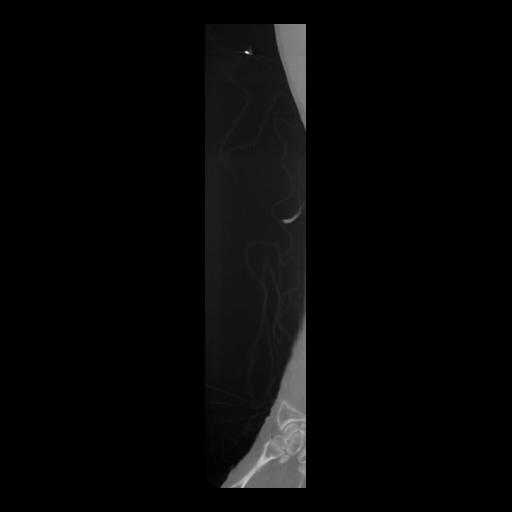

36 CUERPO,CE,Sagittal,3.000,CUERPO,Sagittal,